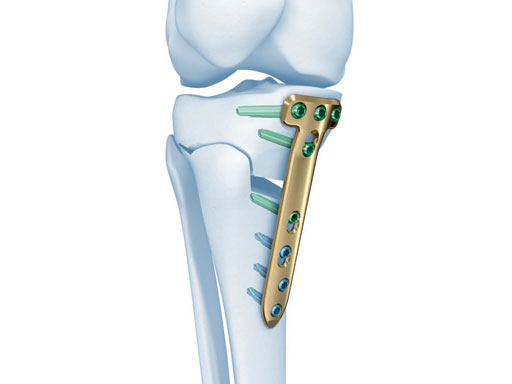

The existing TomoFix medial high tibia (TomoFix MHT) for openwedge osteotomies has been redesigned for better soft-tissue protection and to minimize rotation during compression.

The precontoured plate now has a chamfer at the proximal part and rounded edges at the lateral rims of the plate. A MIPO tapered end at the distal end was added to have a smoother pass to the bone. The two upper LCP holes in the distal part were slightly repositioned in line with the axis of the plate to eliminate the rotation of the plate during compression with cortex screws because of the former asymmetrical alignment of the holes. The two most distal LCP holes were changed to isolated LCP holes to hinder the use of cortex screws.

The correction is planned on a long-leg standing x-ray. After surgery, the mechanical axis should pass through a point 63% on the lateral side of the total width of the tibial plateau in the frontal plane. A transverse or slightly oblique incision is used to avoid damage to the saphenous nerve. The distal fibers of the medial collateral ligament are detached from the tibia. Under fluoroscopic control, two wires are placed in the proximal tibia marking the transverse osteotomy plane. The cut usually starts at the upper margin of the pes anserinus and ends at the tip of the fibula on the lateral side. The wires are placed exactly parallel to the tibial plateau thus taking into consideration the individual tibial slope of the patient. An incomplete cut of the posterior two-thirds of the proximal tibia is performed with an oscillating saw guided by the wires. Continuous irrigation avoids burn injury to the bone. A second osteotomy is now performed in the anterior third of the tibia in an angle of 100 ending above the patellar tendon insertion. A smaller saw blade is used and the complete anterior cortex is cut exactly in the frontal plane. The osteotomy is now gradually opened by inserting flat chisels or a spreader-chisel into the posterior osteotomy cleft. This process may take some minutes and can usually be completed without fracture of the lateral cortex. A bone spreader is now placed in the posteromedial edge of the tibia and the chisels are removed. The leg is extended and the correction is checked with the fluoroscope. A long metal rod is placed between center of the hip joint and center of the ankle joint. The projection of this rod should be at the planned point of correction on the tibial plateau lateral of the midline. Eccentric collapse of the medial joint space may cause accidental overcorrection. In this case pressure on the foot may simulate loading and body weight. The correction can be fine-tuned by opening or closing the spreader. The TomoFix Medial Tibia Plate is now placed in a subcutaneous pocket. The implant is precontoured and usually fits well to the bone surface. The distance holders avoid compression of the medial collateral ligament and the pes anserinus. Three proximal bolts are placed near the subchondral sclerosis zone. The position of the bolts is adapted to the anatomy of the proximal tibia giving optimum purchase for the bolts. An oblique lag screw is inserted distal to the osteotomy. This screw in the first combination hole allows careful compression of the lateral osteotomy hinge and pretensioning of the implant. A stab incision is created on the shaft and the implant is fixed monocortically with bolts. The lag screw and the distance holders are replaced by bolts. The medial collateral ligament is released longitudinally to reduce medial compartment pressure and the wound is closed in layers. An overflow drain may be used. Clinical and experimental work has proven that when this technique is closely followed, corrections up to and over 15 mm can be performed without bone grafting or use of bone substitutes.